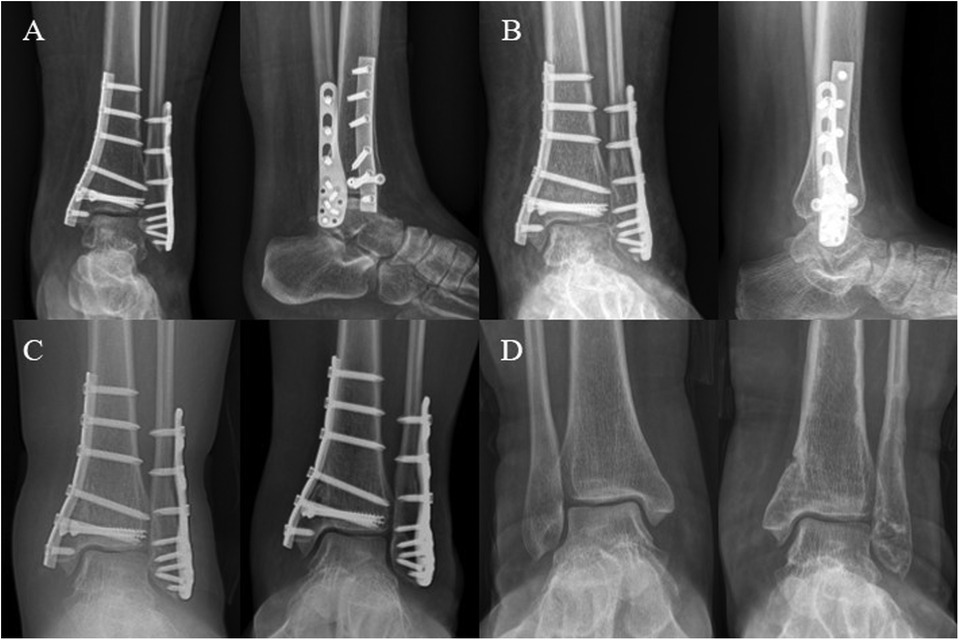

After surgery, the ankle was immobilized with a short-leg cast for 2 weeks, followed by active and passive non-weight-bearing exercises. At 4 weeks, partial weight-bearing was initiated (Figure 2A). Three months postoperatively, DR images showed resolution of the fracture lines in the medial and lateral malleoli, allowing the patient to progress to full weight-bearing (Figure 2B). At 9 and 13 months postoperative follow-ups, the patient exhibited good ankle function with a negative anterior drawer test, achieving an American Orthopaedic Foot and Ankle Society Ankle-Hindfoot Scale (AOFAS Ankle-Hindfoot Scale) of 100, and during the same period, the plate and all screws were removed (Figure 2C). At the 18-month follow-up, the patient's ankle recovery remained consistent with previous outcomes, proving satisfactory (Figure 2D).

Figure 2. This figure illustrates the postoperative follow-up timeline. (A,B) Anteroposterior and lateral DR images at 1 and 3 months post-operation show gradual healing of the ankle fracture. (C) Anteroposterior images at 9 months and 1 year post-operation demonstrate satisfactory alignment of the ankle joint. (D) At 18 months post-operation, anteroposterior images of both ankles show that after removal of the internal fixation, the alignment of the joint remains good when compared to the contralateral joint.